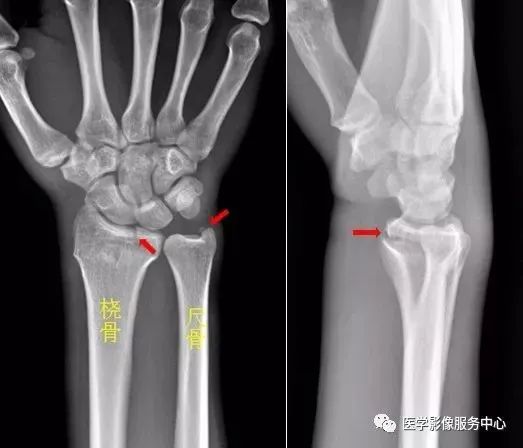

(二)腕关节

1.舟骨  2.月骨  3.三角骨  4.豌豆骨  5.大多角骨  6.小多角骨  7.头状骨  8.钩骨

右侧桡骨远端可见不规则透亮骨折线,并累及关节面,右侧桡骨远端骨折。

尺骨茎突见游离骨碎片影,左侧尺骨茎突骨折。